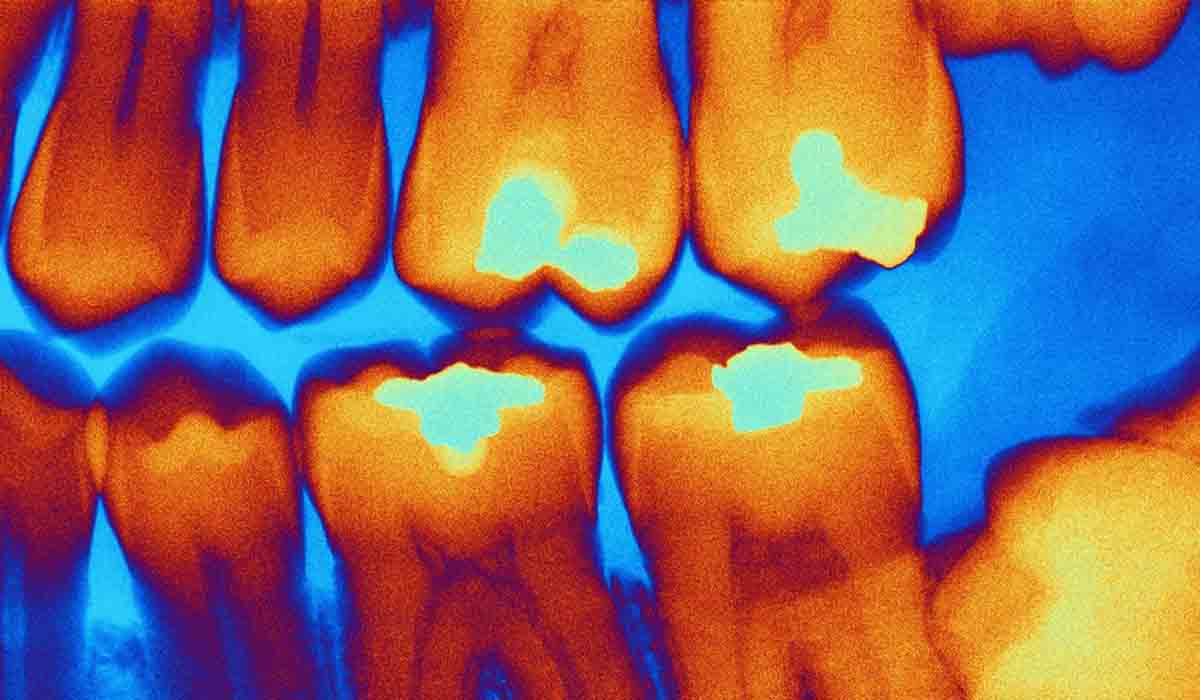

Imagen de ilustración. Foto: RT

Investigadores de la Universidad Sechenov de Moscú han desarrollado un nuevo dispositivo capaz diagnosticar caries durante una cita dental en tiempo real, una tarea que suele resultar difícil incluso para especialistas experimentados.

Según explicó la institución a medios locales, distinguir la dentina infectada por caries, que debe retirarse, de la dentina dañada pero aún viable, que conviene conservar, es uno de los mayores retos en el tratamiento de las caries. Aunque existen tintes especiales que ayudan a identificar el tejido afectado, estos prolongan el procedimiento y requieren pasos adicionales.

El nuevo aparato evita estos inconvenientes gracias a un método no invasivo basado en una sonda óptica que se aplica a la superficie del diente. El dispositivo registra la fluorescencia del tejido y envía la información a un ordenador, donde un modelo de aprendizaje automático determina al instante el tipo de dentina.